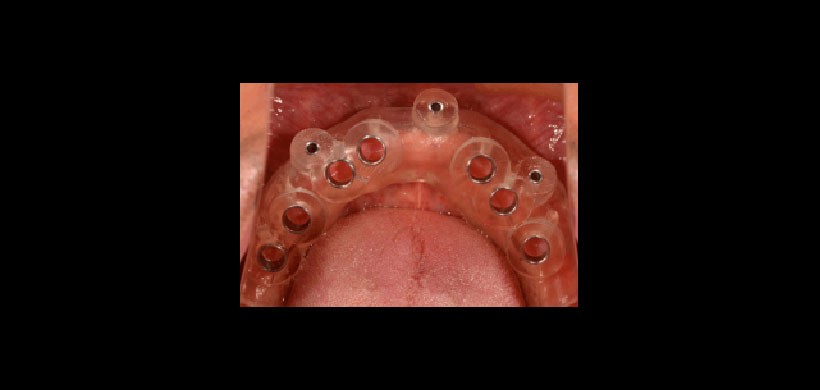

Fig 4. Guía quirúrgica mucosoportada, tiene menos estabilidad.